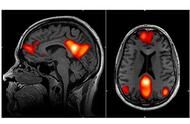

研究:美感在高层脑神经区有统一标准

新研究发现,人类大脑对不同类别的美,比如画作、建筑物或自然风光,在视觉区域有着不同的反应;然而在一个负责静思的区域,居然呈现一致的反应。研究者让受试者欣赏画作、建筑或自然风光的图片,并用功能性磁振成像(fMRI)监控受试者脑部的活动。